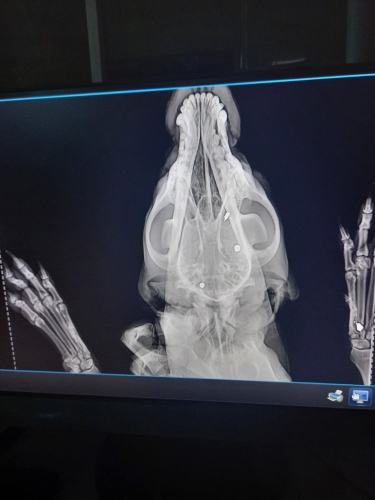

Оренбурженка связалась с волонтёрами приюта "Я - Живой". Удалось найти автомобиль, свозить животное в ветклинику. Как оказалось, её расстреляли из охотничьего ружья. В теле обнаружили 19 дробин. Не было практически ни одного живого места: повреждены голова, лапы, позвоночник, грудь, горло, живот, глаз. Врач отметил, что если бы стреляли с более близкого расстояния, то шансов выжить у бедной собаки не было бы...

Вопрос об операции будет решаться после того, как ее состояние стабилизируется, ей нужно отогреться, так как два дня она пролежала в снегу, проколоть антибиотики, подождать сокращения матки и остановки кровотечения. Одно точно: левый глаз, залитый кровью, видеть не будет, дробь повредила его полностью, - отметили волонтеры.